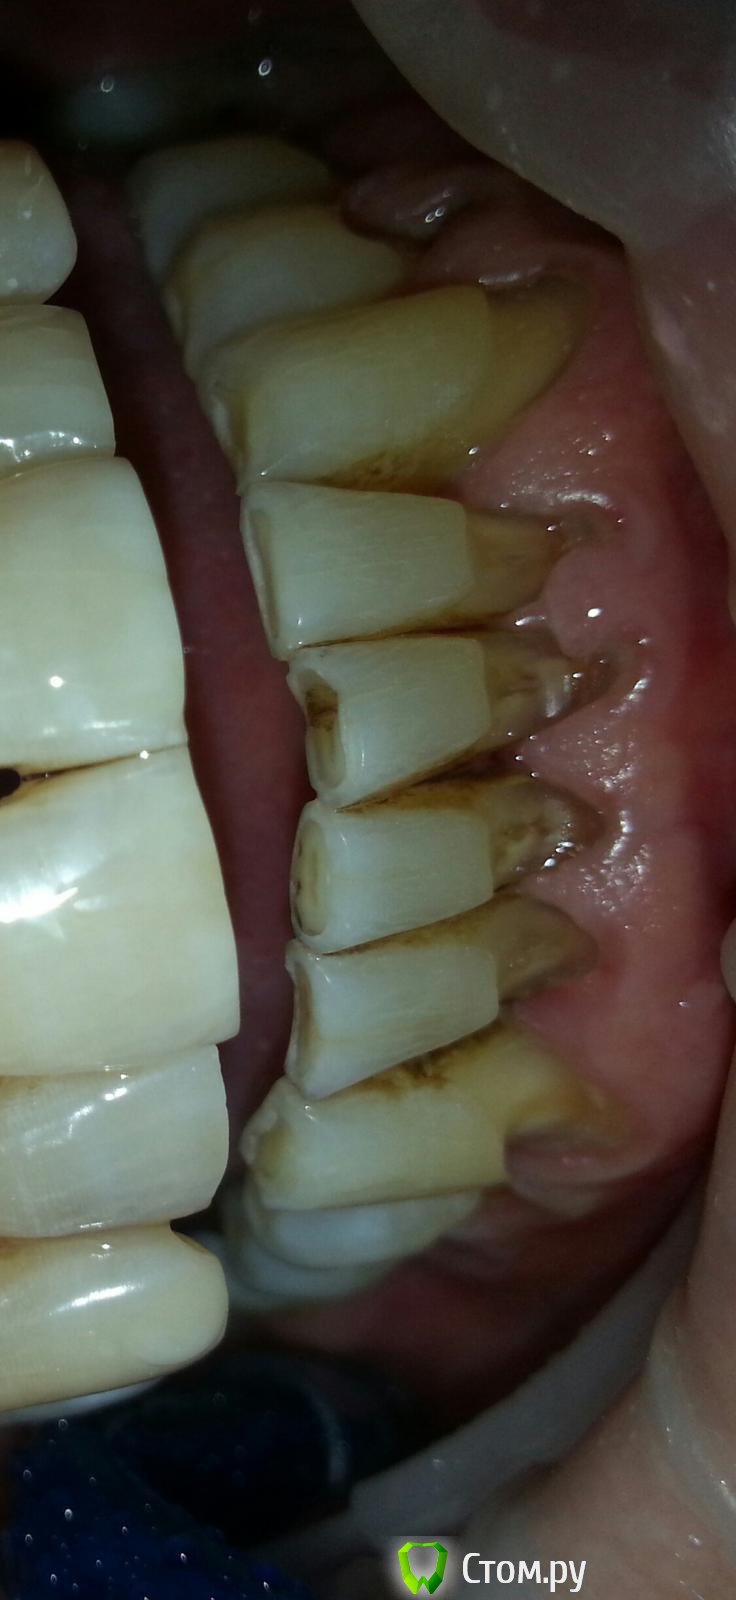

Антонина Николаевна Опубликовано 26 февраля, 2014 Поделиться Опубликовано 26 февраля, 2014 Сплошные клиновидные дефекты((((( пациенту 55 лет Ссылка на комментарий

Антонина Николаевна Опубликовано 26 февраля, 2014 Поделиться Опубликовано 26 февраля, 2014 21 запломбировала Еnamel hri plus Ссылка на комментарий

Гарриевич Опубликовано 26 февраля, 2014 Поделиться Опубликовано 26 февраля, 2014 (изменено) Мне кажется что тут нужно искать другое решение, чем композитное восстановление. Если прикинуть размер коронки резца, то вы восстанавливали композитом уже выше ЦЭС Ps цвет подобрали прилично Изменено 26 февраля, 2014 пользователем Гарриевич 1 Ссылка на комментарий

Антонина Николаевна Опубликовано 2 марта, 2014 Поделиться Опубликовано 2 марта, 2014 Спасибо. ))))сегодня пациент признался что ему раньше не хватало щетки на 2 недели. Он ее просто "убивал" после чистки. Ссылка на комментарий